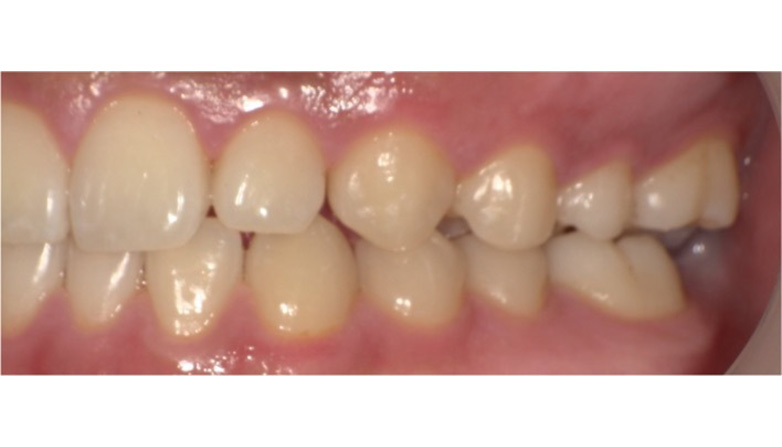

症例3

before

after

| 主 訴 | 着色を落としたい |

| 治療期間 | 通院 1回 |

| 治 療 費 | 1回 7,700〜11,000円(税込) |

| 治療内容 | PMTC |

| 治療のリスク | 歯自体の色を白くすることはできない。 しばらくすると再び着色することがある。 |